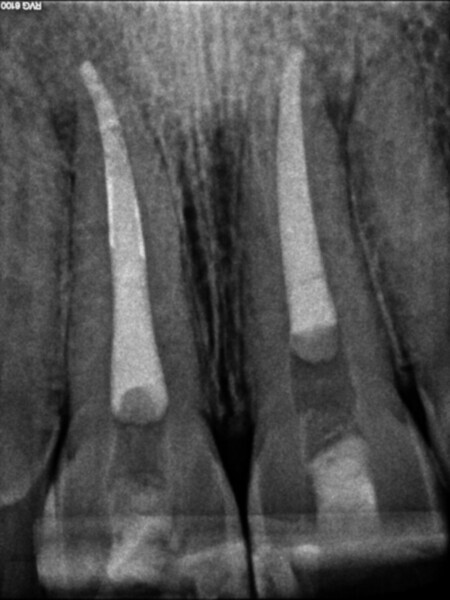

Irrigating the root canal: A case report